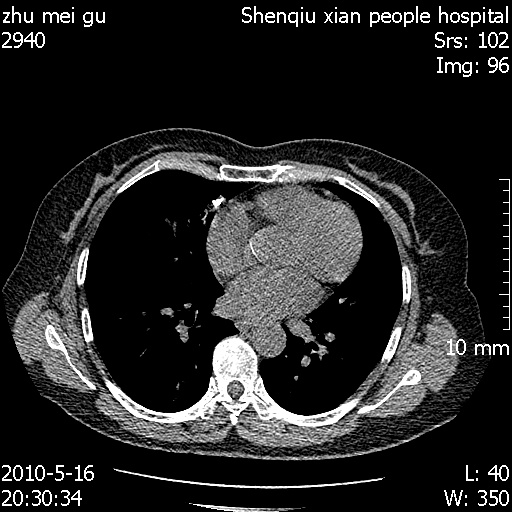

标题: CT26733:能否诊断支扩?

患者,女,62岁,有反复咯血史10年,近三年来大咯血数次,每次量在500-1000ml

图像不全。右中叶内侧段纤维、钙化灶。

没看到支气管扩张的证据

you右肺中叶有点支扩 但不至于咳那么多血啊

图像不全。右中叶内侧段陈旧性病灶。

右中叶内侧段慢性感染性病变,不排除合并支气管扩张可能。

建议hrct